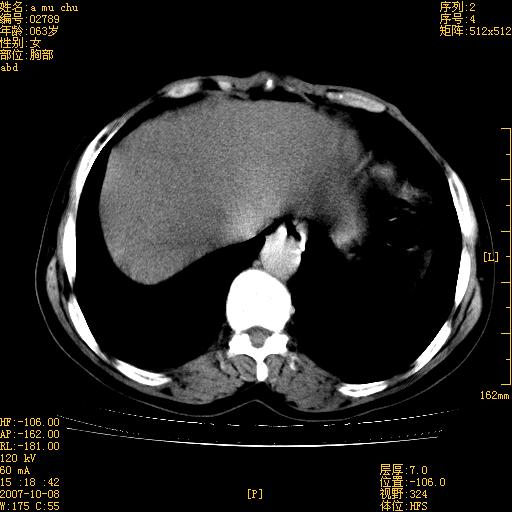

以下是引用王维浦在2007-10-17 21:02:00的发言:[br]胆囊增大,囊壁明显不规则增厚,邻近肝组织浸润,肝内外胆管无扩张。诊断:胆囊ca;[br]胰头软组织肿块影,考虑是由转移肿大的胰后淋巴结、没有肠道准备的十二指肠及胰头共同形成。[br]

以下是引用zhangzexing在2007-10-18 7:13:00的发言:[br]支持胰头占位,慢性胆囊炎. 2.肝左叶前外侧段占位,血管瘤?建议增强

以下是引用影像实习生在2007-10-17 19:49:00的发言:[br]支持胰头占位,慢性胆囊炎. 2.肝左叶前外侧段占位,血管瘤?建议增强.

以下是引用刘振江在2007-10-17 19:42:00的发言:[br]没有增强,胰头癌?胆囊及肝左叶占位?